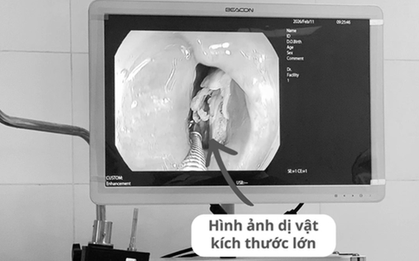

Bệnh nhân 16 tuổi đau họng kéo dài, bác sĩ phát biện bí mật "đáng sợ" bên trong

Bệnh nhân Đ.A.T. (16 tuổi) nhập viện với biểu hiện nuốt đau, nuốt vướng, đau rát vùng cổ. Các bác sĩ gắp ra dị vật kích thước lớn 2x4cm, hai đầu sắc nhọn trong thực quản bệnh nhân.